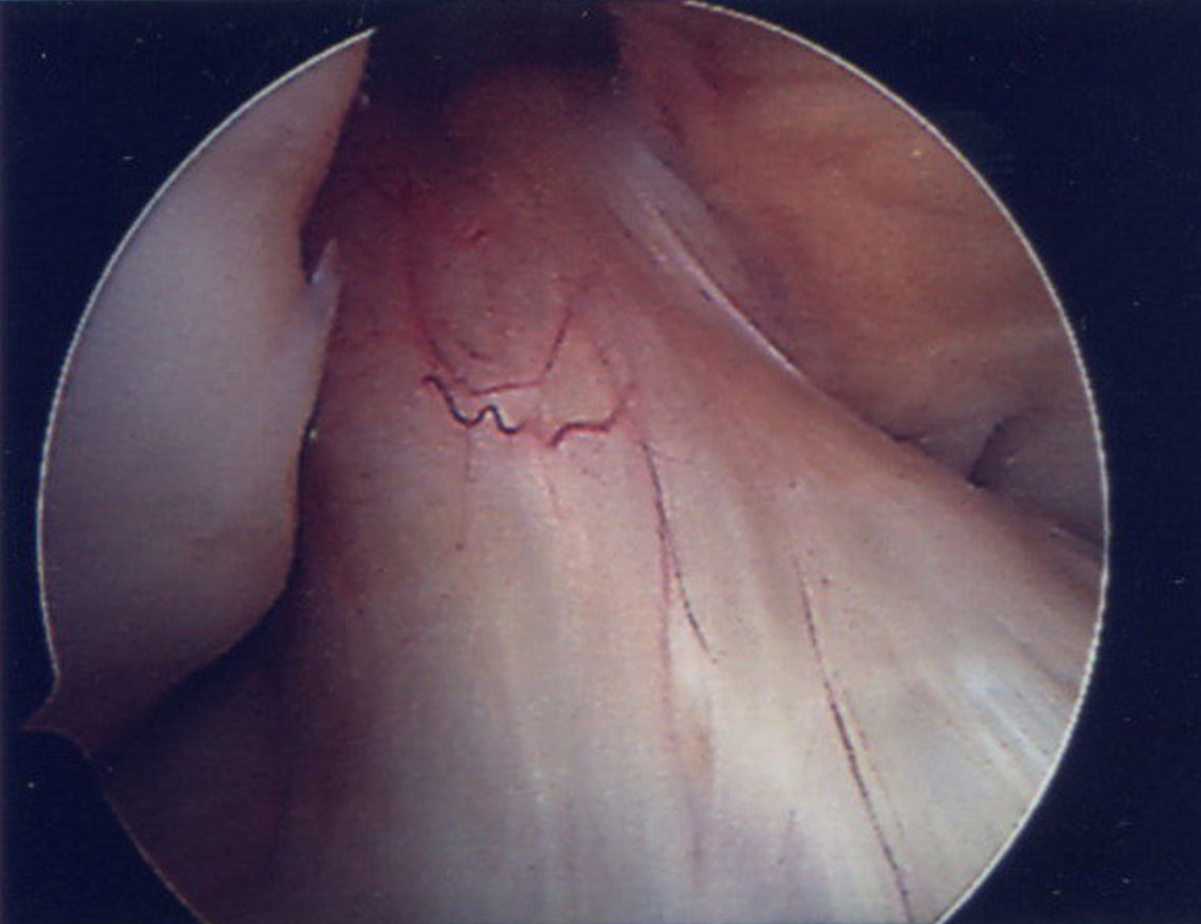

The term arthroscopy refers to a type of “keyhole” surgery that is used to diagnose and treat joint problems. By far the most common joint to undergo this procedure is the knee. The operation may be carried out under general or spinal or even local anaesthetic depending on the indication for surgery, patient factors, and the surgical team’s preference. During the procedure small incisions are made on either side of the knee joint. An arthroscope (a small metal tube with a camera, which projects images to a TV screen) is inserted through one of the incisions allowing the surgeon to examine the knee joint from the inside. Specially developed instruments such as probes and precision tools may be inserted through other incisions allowing the surgeon to treat a range of conditions that occur within the knee joint.

The video below shows a detailed explanation of the causes and presentation of Knee Arthroscopy. They show a basic outline of the procedures used by Amir Qureshi and after care required in order that you, the patient, may recover to your full fitness once again.